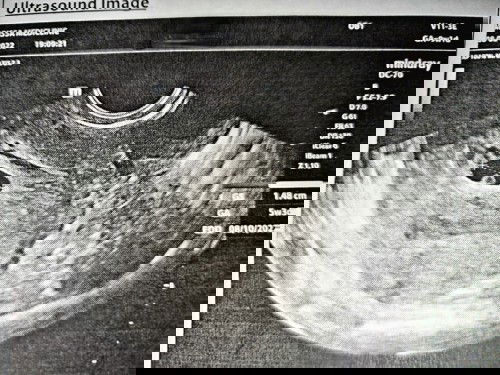

LMP sy 6/12/2021 n spttnya sy dh 9minggu1hari...tp bila g scan td...bru 5week3hari.....jarak ngn LMP tu dh 4 minggu..ade masalah ape2 x? n stu lg...esok dh temujnji utk bukk buku pink sbb nurse buat tmujnji berdsrkn tarikh LMP sy....dh confius bila tgk scan 5week ni nk g bukak buku kt kk ke atau hold dlu...pendpt ibu2?#seriusnanya #ingintahu